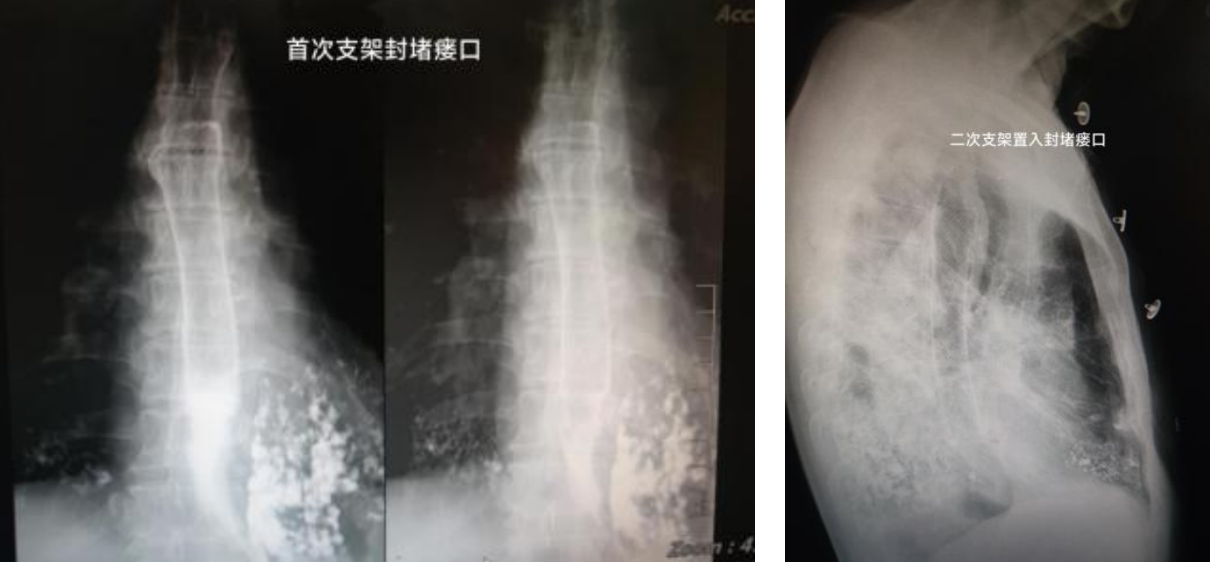

患者9个月前被诊断为食管癌,因不想做手术,间断在省级医院行放化疗。4个月前,患者出现进食哽噎伴喝水明显呛咳情况,因放疗后患者食管韧性降低,致使行食管支架治疗时穿孔等风险增高,首诊省级医院建议保守治疗。可艰难的生存状况让患者无法继续忍受,为此选择就诊于我院。入院后消化科医师团队给患者完善检查后发现,该患者存在食管肿瘤梗阻,并发“食管气管瘘”,严重影响进食及生活质量。经科室综合评估病情后,一致认为提高肿瘤患者生存质量是目前最需要做的事,这名患者的治疗虽然难度高、风险大,但没有明显禁忌症,且手术一旦成功患者的问题就能解决。主任医师周明向患者及家属详细交代病情及治疗方案后,家属同意由我院消化科行食管支架置入术,功夫不负有心人,手术很成功,患者呛咳症状消失,可正常进食半流质饮食,症状好转出院。

然而,半个月前该患者再次出现饮水呛咳症状,就诊于省级医院完善检查后未发现明显瘘口,该医院建议继续到我院就诊,故再次收治于我院消化科。入院后周明主任仔细为患者查体、询问病史,结合丰富的临床经验,周主任判断该患者再次发生食管气管瘘,决定再次放置食管覆膜支架解决问题。告知诊疗方案后患者及家属均表示同意,积极术前准备后消化科再次成功置入食管支架,术后患者呛咳等症状立马消失,临床症状好转出院。